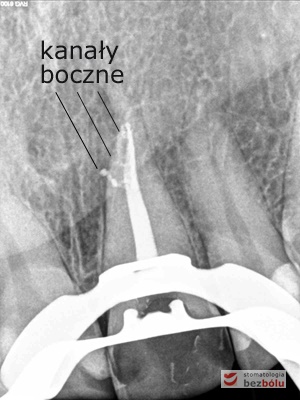

Pacjentka lat 37 zgłosiła się z silnymi dolegliwościami bólowymi siekacza centralnego na górze po stronie lewej. Ząb był w trakcie leczenia kanałowego w innej placówce. Jedno wizytowe leczenie kanałowe polegało na starannej instrumentacji kanału korzeniowego oraz wypłukaniu podchlorynem sodu, a następnie starannym odtłuszczeniu i wysuszeniu systemu korzeniowego. Kanał został szczelnie zamknięty metodą termokondensacji ciśnieniowej przy pomocy instrumentarium, tj. system B i Obtura. Kontrola radiologiczna potwierdziła szczelność wypełnienia oraz ujawniła obecność kanałów bocznych, które bez starannego wypełnienia mogłyby stać się przyczyną infekcji w obrębie wyrostka zębodołowego. Wypełnione kanały boczne przypominały dymiące fabryczne kominy. Leczenie zostało zakończone odbudowaniem zrębu koronowego z udziałem ćwieka z włókna szklanego, który został otulony materiałem kompozytowym nanohybrydowym. Jedno wizytowe sprawne leczenie endodontyczne przyniosło pacjentce natychmiastową ulgę, a odbudowa korony zredukowała ryzyko złamania zęba.